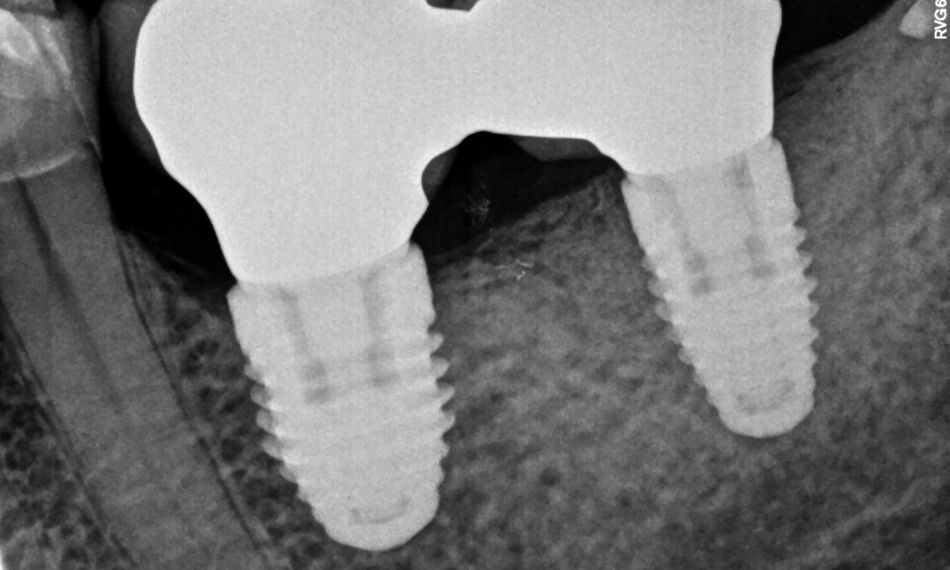

Für die einleitende konservative Therapie wurde die prothetische Versorgung entfernt. Auf die Implantate wurden Gingivaformer platziert (Abb. 1, 2). Für das nichtchirurgische mechanische Debridement wurden herkömmliche Ultraschallinstrumente und ein Pulver-/Wasserstrahlreiniger verwendet. Anschließend wurde der Situs mit CHX 0,12 % und Metronidazol 5 mg/ml und einer Lösung aus einem lokalen Antibiotikum und Hyaluronsäure gespült. Von den Implantaten in Regio 36 und 37 mit den platzierten Gingivaformern wurde eine Röntgenaufnahme angefertigt (Abb. 3).

Nach einer Einheilzeit von 6 Monaten wurden Röntgenaufnahmen angefertigt. Diese zeigten ein optimales periimplantäres Knochenniveau (Abb. 16, 17). Um das über die Gingivaformer gewachsene Knochengewebe zu entfernen, wurde ein Gewebelappen abgehoben (Abb. 18, 19). Der Wundverschluss erfolgte mit Nahtmaterial Vicryl® 4/0 und Prolene 6/0, um die Inzision sicher und wirksam zu verschließen. anschließend wurde die prothetische Versorgung wieder sorgfältig auf die Implantate geschraubt (Abb. 20).

Zehn Tage später kehrte die Patientin zur Nachuntersuchung zurück in die Praxis und der behandelte Bereich wurde gründlich untersucht und beurteilt. Bei diesem Termin wurden die Nähte vorsichtig entfernt. Zusätzlich wurde eine Röntgenaufnahme angefertigt, um die knöcherne Regeneration und die Heilung des behandelten Bereichs zu beurteilen. Die Patientin war mit dem Behandlungsergebnis zufrieden und zeigte ein erfolgreiches und positives Ansprechen auf die Therapie (Abb. 21).